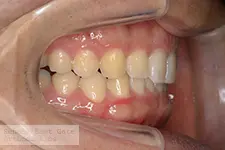

4本の先天性欠如歯と、2本の埋伏歯を有し、開窓牽引と空隙閉鎖を行うことで欠損部補綴を行わないで咬合再構成を図った空隙歯列症例

| 主訴 | 出っ歯と前歯の隙間が気になる。奥歯の隙間を閉じて欲しいが、矯正歯科治療後にブリッジ補綴やインプラント補綴などはやりたくない。矯正歯科治療だけで隙間を閉じて歯並びを仕上げてほしい。 | ||

| 年齢・性別 | 13歳未成年男性 澤村 悠里様 | 治療に用いた主な装置 | マルチブラケット |

| 抜歯部位 | 下顎左右5番 | 治療期間 | 4年 |

| 治療回数 | 69回 | 治療費 | 120万円~140万円 |

| 治療内容 | 4本の先天性欠如歯と2本の埋伏歯を有していたため重度の空隙歯列を呈していました。初診時年齢が13歳であったため、下顎骨の成長が長期に継続することが予測され、2期分離治療による矯正歯科治療を行ないました。 | ||